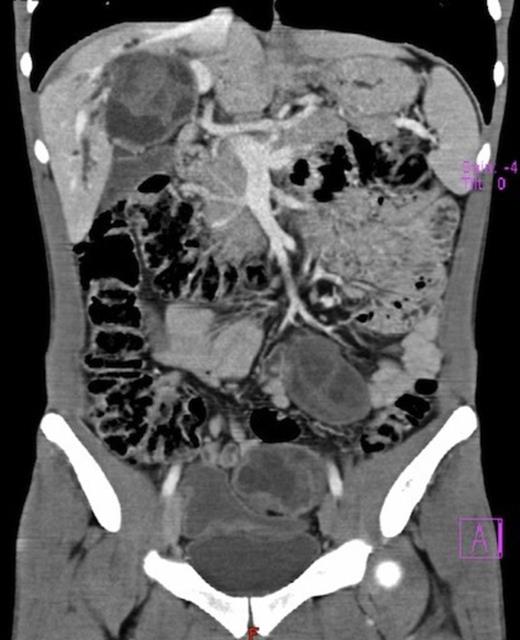

Abdominal CT scan: multiple hydatid cysts in the right lobe of the liver, one of them near the hepatic confluence

Laboratory investigations showed a slight anaemia, elevation of serum bilirrubin (conjugated 10.6 mg/dl), alkaline phosphatase (959 U/L), gamma-glutamyl transpeptidase (755 U/L). Hydatid serology was positive. Abdominal ultrasound demonstrated multiple cystic lesions spread in the liver, splenic hilum and peritoneal cavity. CT-scan confirmed the presence of numerous hydatid cysts, in different stages of development (type I-IV of Gharbi Classification), ranging from 3 to 8 cm in diameter, with 3 involving the right lobe of the liver and segment 4 (Fig.1). The splenic hilum contained a 4 cm cyst, and 9 more cysts were described in peritoneal cavity: near the gallbladder, in the root of the mesentery, in the right iliac fossa and in the Douglas pouch (Fig. 2). Cholangio pancreatography (MRCP) showed intra-hepatic bile ducts dilatation. Cholangiography (ERCP) was attempted without success. Pre-operative albendazole therapy (10 mg/Kg) was prescribed for 4 weeks.